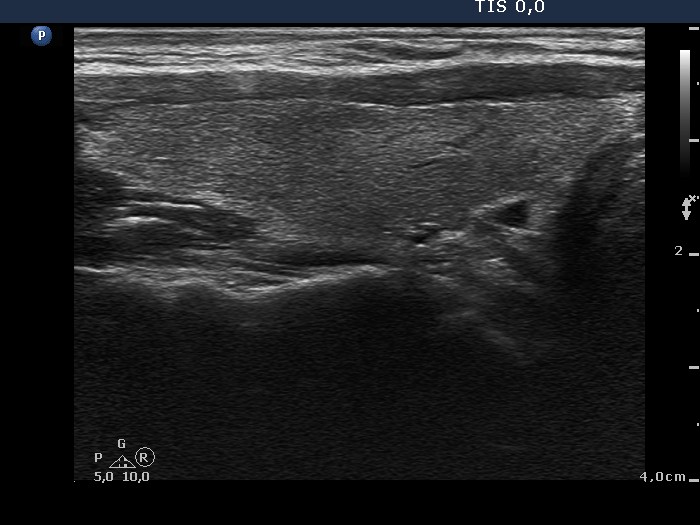

Extrathyroidal spread - case conp 032 (ultrasonographic picture 2)

Right lobe, longitudinal scan. There are several minimally hypoechogenic areas, the presence of which raises the possibility of lymphocytic thyroiditis.